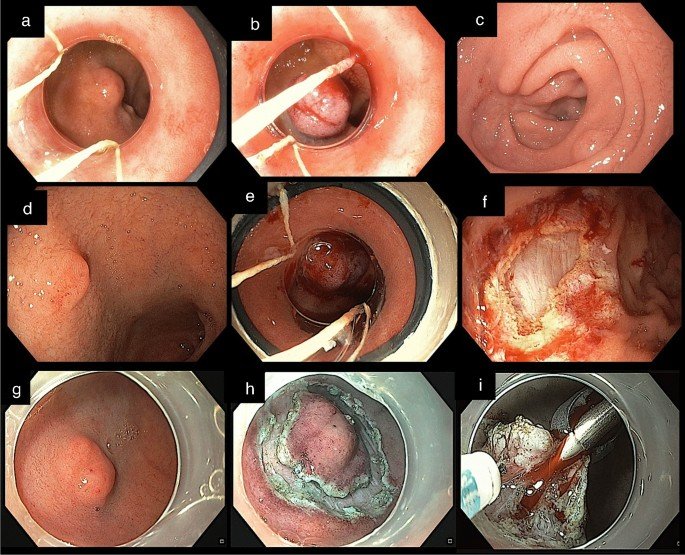

- Administering a small dose of I-131 orally allows it to be absorbed into the bloodstream through the gastrointestinal tract. The thyroid gland then concentrates the radioiodine, initiating the destruction of its cells. Any surplus radioiodine is primarily eliminated through urine, swiftly exiting the body. This therapy is highly effective for managing hyperthyroidism and is often the preferred treatment.